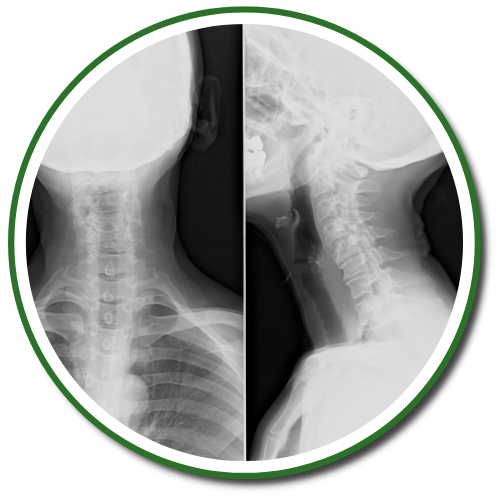

Chiropractors take x-rays to see the internal condition of the spine. X-rays also reveal if there are any underlying spinal disorders, such as arthritis of the spine, abnormal development, disc disorders, bone spurs, and spinal deterioration.

Having an x-ray taken before any adjustment helps chiropractors make a correct diagnosis. Combining x-rays with other exams will benefit the patient ultimately.